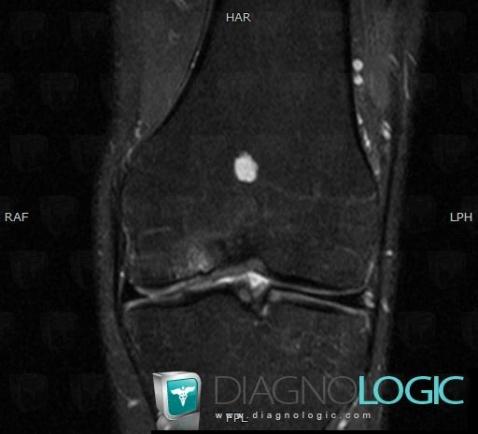

Enchondrome, Fémur -inférieur, IRM

Voici les informations spécifiques à l'image clé ci dessus:

- Diagnostic Enchondrome, Localisation(s) Fémur - 1/3 inférieur, comportant les gammes Lésion osseuse en franc hypersignal T2, Syndrome de remplacement médullaire